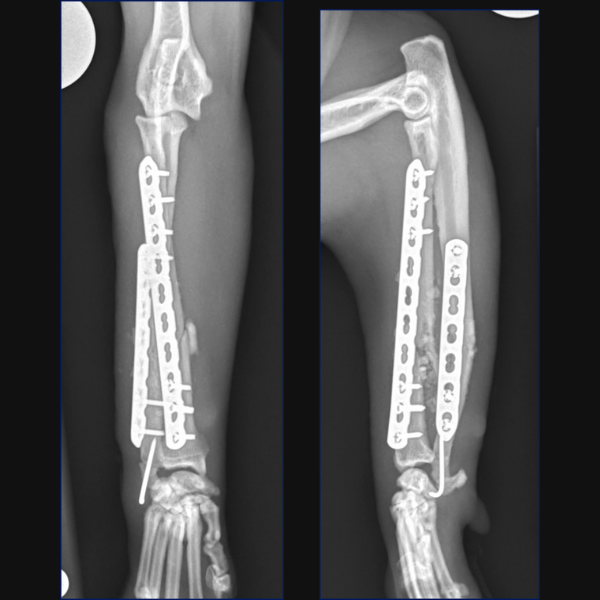

For Bundle we performed open reduction and internal fixation using a 14-hole 1.5/2.0 Veterinary Cuttable Plate (VCP) on the radius and a 6-hole 1.5mm Locking Compression Plate (LCP) on the ulna. This was all performed through single craniolateral approach. I think we have addressed one reason why we chose dual bone fixation in this case, due to the lower complication rate that could be anticipated with that. Another reason is that in people at least, insufficient stabilization has been associated with an increased risk of synostosis formation so rigid, dual-bone fixation was desired here to limit that. But why choose a lateral plate on the ulna rather than an IM pin?

You could debate the choice of a single approach for fixation here based on some literature in the human field. I have generally preferred a single approach with the suture line not lying directly over either of my implants but that is simple personal preference. While it is based on a very specific posterior approach to the radius and ulna called the Boyd approach, and may not be transferrable to our feline patients, there is some evidence in humans with radius-ulna fractures that placement of dual bone fixation through a single approach is associated with a higher risk of synostosis formation than placement of implants through two separate approaches. Postulated reasons include extensive soft-tissue exposure, increased risk of development of radioulnar hematoma or interosseous damage and potential malpositioning of one of the implants due to suboptimal exposure of both bones. Further research is required to determine whether single or dual approaches may be associated with different complication rates in cats, but certainly, you could argue that the radial plate is positioned slightly too laterally at the proximal extent here and that a single approach may have contributed to that.

In terms of critiquing my postoperative radiographs here from Figure 3, in addition to the radial plate being slightly too lateral at the proximal extent, the first screw distal to the fracture is close to caudodistal extent of the short oblique fracture line. This may have rendered this screw monocortical and additionally, may have caused some fragmentation of the fracture line at this point, so not ideal, but we do have an additional three bicortical screws distally on the radius in addition to three screws in the ulna so I did not consider that this warranted any immediate revision surgery.